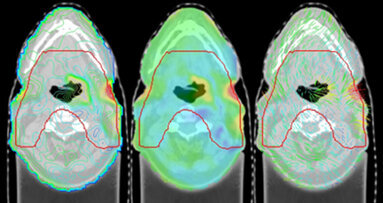

Bei der Therapie von Kopf- und Hals-Karzinomen werden Krebszellen durch Bestrahlung an der Zytokinese gehindert – allerdings hemmt die Therapie auch die Teilung der Mundschleimhautzellen. Die Störung des Regenerationsprozesses begünstigt insofern Schädigungen, da nun Bakterien ungehindert in das Gewebe eindringen können. Für Patienten sind die Nebenwirkungen äußerst schmerzhaft. Nicht nur die Nahrungsaufnahme, sondern auch das Trinken, Schlucken und Sprechen wird zur Qual.

Forscher des Mangalore Institute of Oncology scheinen ein wirkungsvolleres Mittel als die konventionelle Gabe von Povidon-Jod gefunden zu haben: Honig. Die in Foods veröffentlichte Studie beweist, dass Honig die Entwicklung von oraler Mukositis abschwächen kann – ohne dabei negativen Einfluss auf die Strahlentherapie zu nehmen.

In der Studie wurden 50 freiwillige Patienten eines Therapiezentrums für Kopf- und Nackenkrebs zufällig zwei Gruppen zugeordnet. Die Kontrollgruppe wurde mit Povidon-Jod versorgt. Die andere Gruppe erhielt die Instruktion, Honig dreimal täglich – eine Stunde vor und zwei bzw. sechs Stunden nach der Bestrahlung – aufzutragen. Ein Pathologe, der nicht über die Behandlungsmethode in Kenntnis gesetzt wurde, beurteilte anhand einer vierstufigen Skala in regelmäßigen Abständen den Schweregrad der Mukositis.

Im Vergleich zur Behandlung mit Povidon-Jod entstand in der „Honiggruppe“ signifikant seltener Mukositis. Zudem verzögerte sich die Entwicklung, und der Schweregrad ging zurück. Da die Nebenwirkungen der Strahlentherapie für die Patienten „erträglicher“ wurden, konnte die Therapie auch ohne Unterbrechungen durchgeführt werden – die Behandlungsdauer verkürzte sich ebenso.